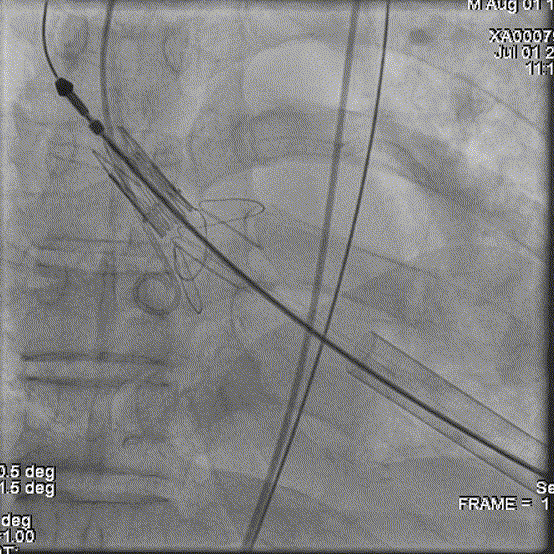

猪尾导管置于右冠窦行根部造影(右冠窦向右侧转位):

穿刺置入导丝,建立轨道。定位件进入对应窦部: